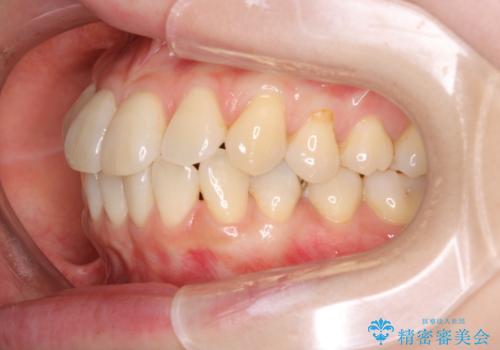

- インビザラインで非抜歯治療を行いました。IPRと拡大をし、叢生、咬合をきれいにしました。

主訴であったかみ合わせを正しい位置に動かし、バランスよくかめるようになりました。矯正治療終了後にメタルインレーをセラミックインレーに替えました。